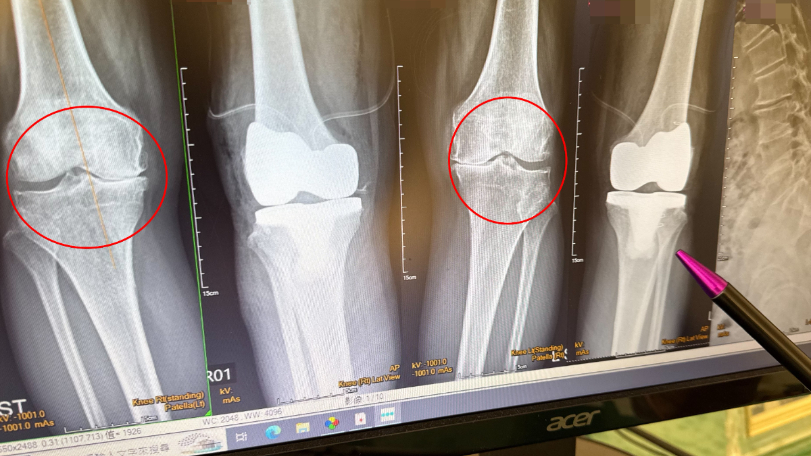

大甲李綜合醫院副院長、骨科主治醫師王芳英表示,患者是第四期的退化性關節炎,雙腳內翻變成10度,外觀看起來呈現O型腿,腳無法伸直,另外脊椎第2到第5節滑脫長骨刺,背部往前傾。門診時,患者非常困擾,詢問「我到底要先治療雙膝還是脊椎」,他分析後建議先置換人工膝關節。

王芳英進一步說明,患者雙膝變形嚴重無法站直,如果沒有先開刀治療,背部會持續往前傾,同時向患者建議,一次進行雙腳的膝關節置換,避免完成單腳人工膝關節置換後造成長短腳,在身體重心不穩走路下,讓脊椎滑脫的症狀更加嚴重。患者在置換雙膝後,隔天便能下床正常走路。